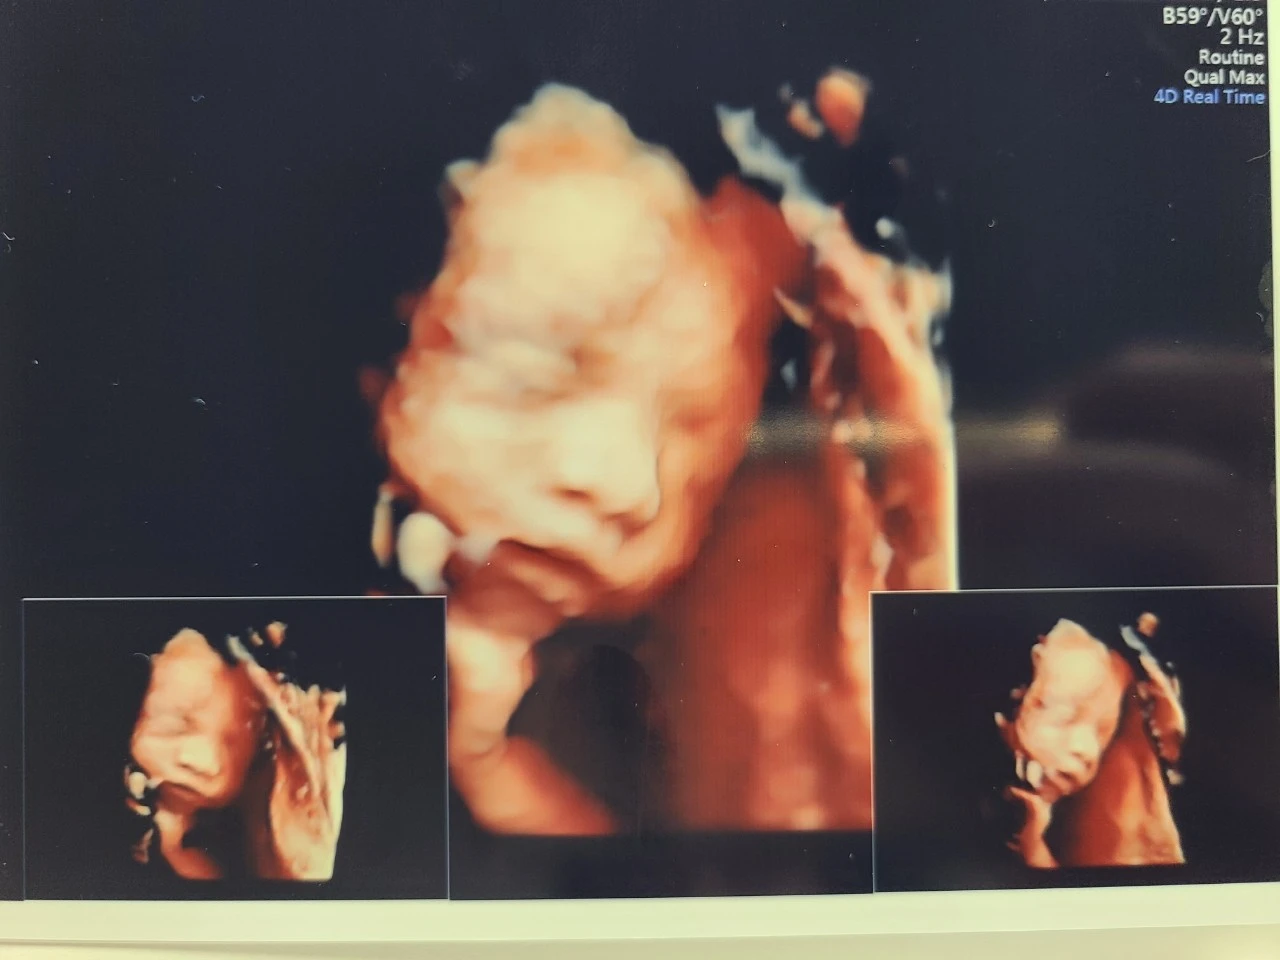

26주 차 검진에서는 임당 검사뿐만 아니라 초음파 검사도 받았어. 한 달 전보다 훌쩍 자랐을 너의 얼굴을 볼 기대에 엄마 아빠 모두 들떠있었어. 그런데 이런 우리 마음을 아는지 모르는지 너는 연신 팔과 손을 올리며 얼굴을 보여주지 않더구나. 초음파 선생님도 답답하셨는지 네가 팔을 내리길 기대하며 엄마 배와 옆구리를 쿡쿡 찌르셨지. 한참의 노력과 기다림 끝에 마침내 살이 포동 하게 오른 네 얼굴을 볼 수 있었어. 그런데 어쩜, 아빠를 꼭 닮은 모습에 엄마는 웃음이 터져버렸어. 첫 딸은 유독 아빠를 닮는다더니 그 말이 진짜였나 봐.

딱풀이 너의 얼굴 지분은 네 아빠에게 모두 뺏겼지만 손발이 모두 크고 손가락이 유난히 긴 거는 엄마를 닮은 게 분명해. 발이 큰 건 딱히 환영할 만한 일은 아니지만. 어쨌든 한 달 만에 초음파를 통해 건강하게 잘 자라고 있는 네 모습을 확인할 수 있어서 엄마는 참 감사했어. 고맙고 사랑해 딱풀아~